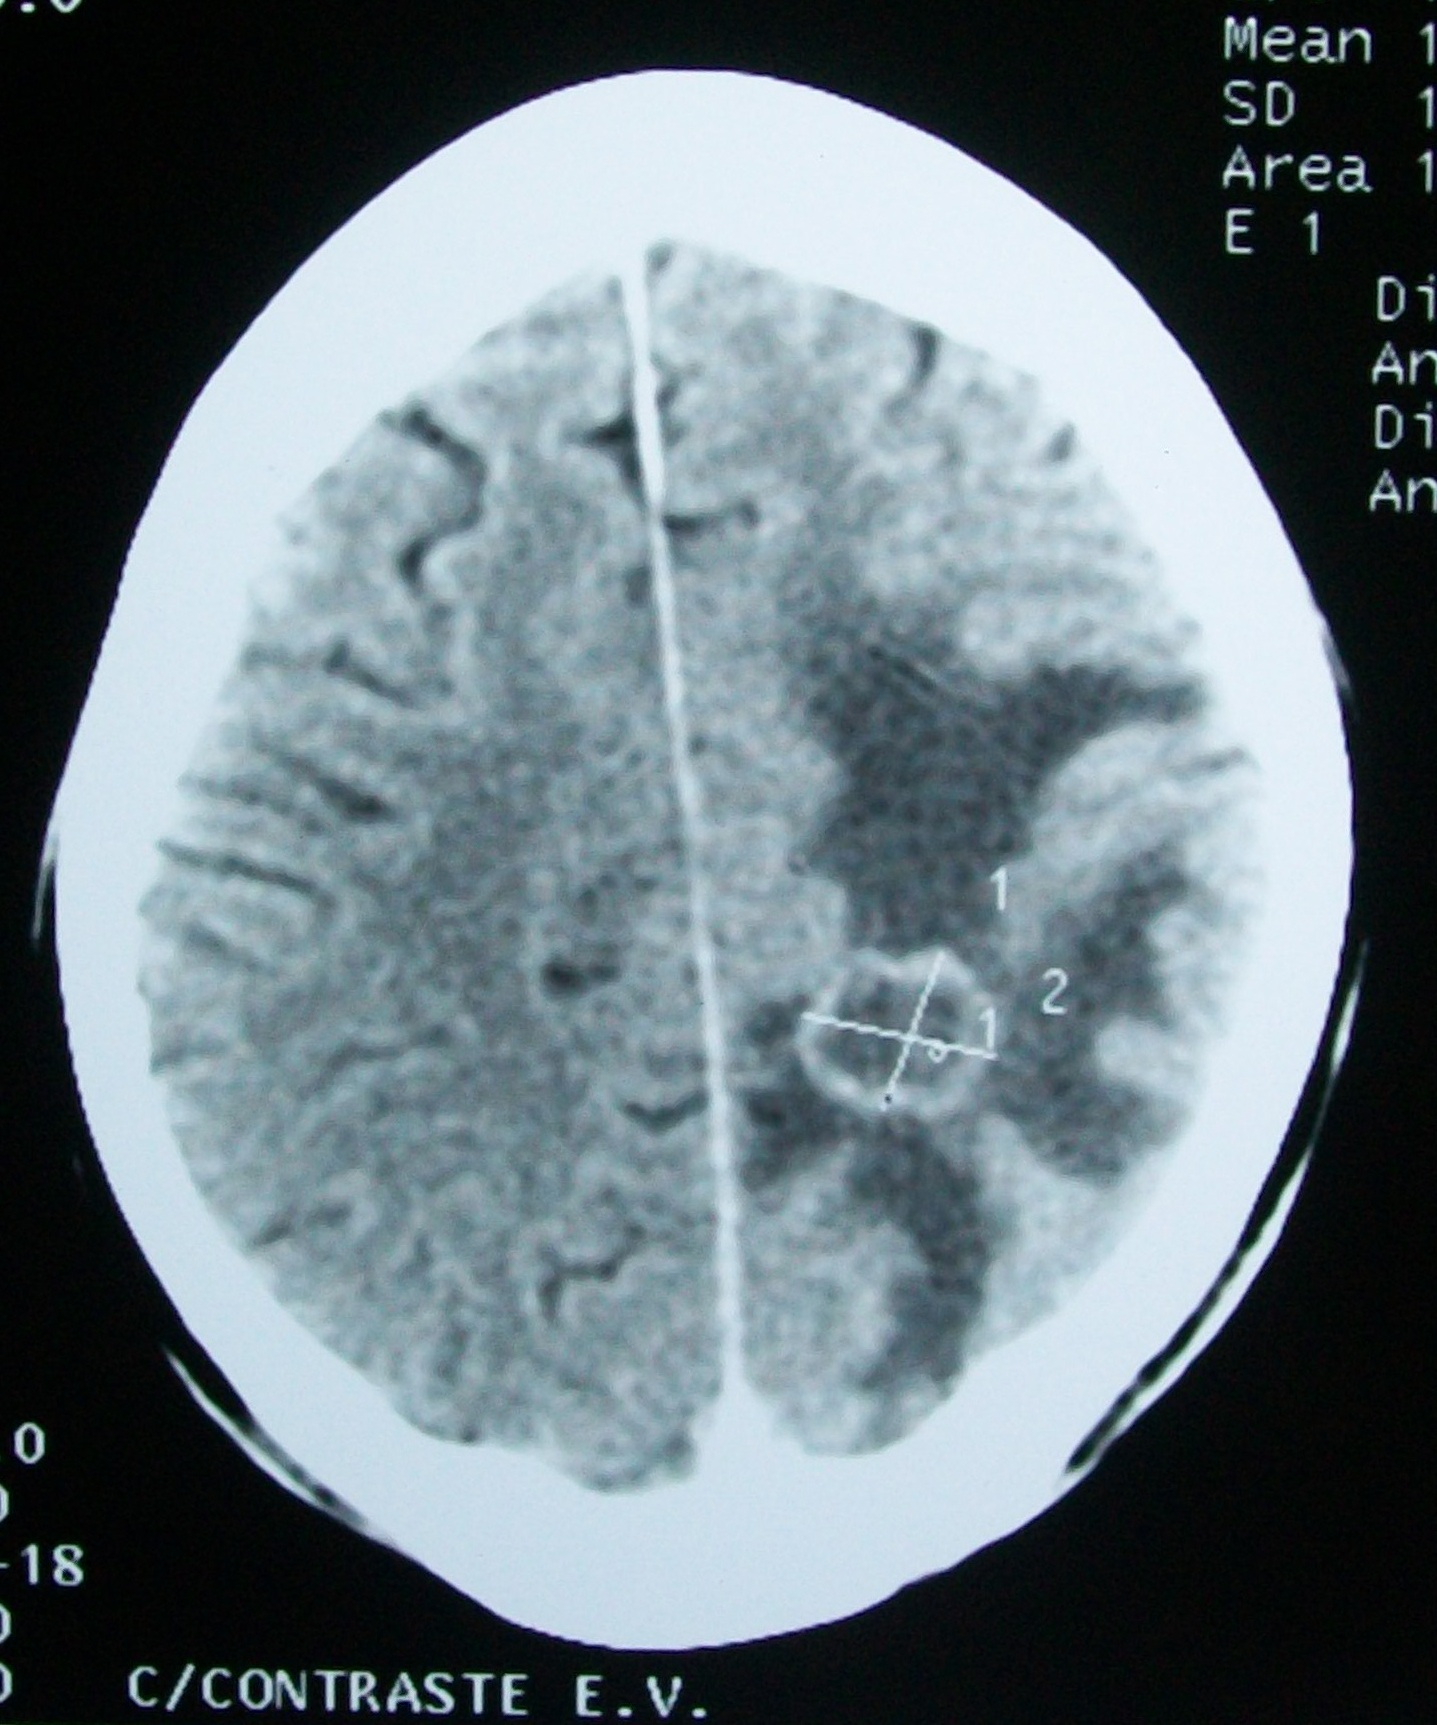

SCP-4425发展早期的CT扫描成像

描述: SCP-4425是指一个人的颅内区域自行出现大量铝的现象。铝主要围绕着受试者的大脑生长直到最终包裹住受试者的整个大脑。据观察,在完全包裹受试者的颅骨区域之前,这一过程会潜伏一段时间。2